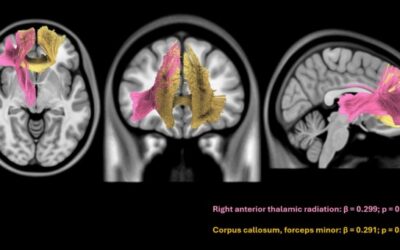

Impact of cardiometabolic factors and AD plasma biomarkers on white matter hyperintensities volume in individuals with cognitive complaints from the global south.

Riquelme-Contreras P, Henriquez F, Gonzalez-Campo C, Altschuler F, Fraile-Vazquez M, Ferreira PCL, Bellaver B, Karikari TK, Pascoal TA, Okuma C, Gonzalez-Billault C, Court FA, Cerda M, Lillo P, Durán-Aniotz C, Khondoker M, Hornberger M, Slachevsky A. Impact of...